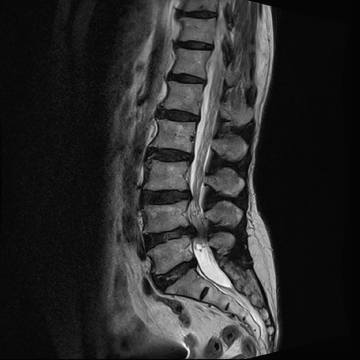

요추 협착증 수술 전·후

2020.08.30

2022.09.06

ㆍ환자 동의를 받은 자료이며, 이미지 사진은 실물과 다를 수 있습니다.

ㆍ모든 자료는 새움병원 자료입니다.